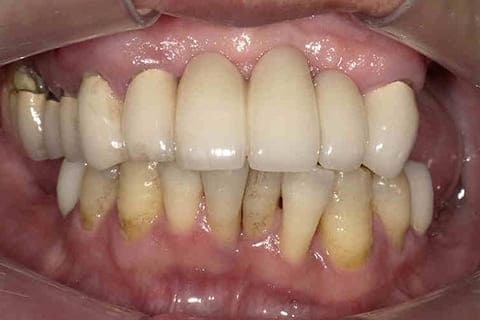

歯がなくても諦めない

オールオン4

無歯顎(歯がない)の方でも、歯が数本しかない方でも諦めないでください。

入れ歯と違い見た目も良く、しっかり噛むことができ、発音良く話せる、

オールオンフォー(All on 4)インプラント治療があります。

このオールオンフォーは、最小4本のインプラントによるブリッジ治療となります。

1日で治療が完了するので、即日にしっかりと噛める歯になります。

健康に美しく臨床実績集

虫歯や歯周病、事故などでの欠損、

噛めるようになりたい、見た目の美しさの追求など、

審美的に機能的に回復した治療経過報告症例です。